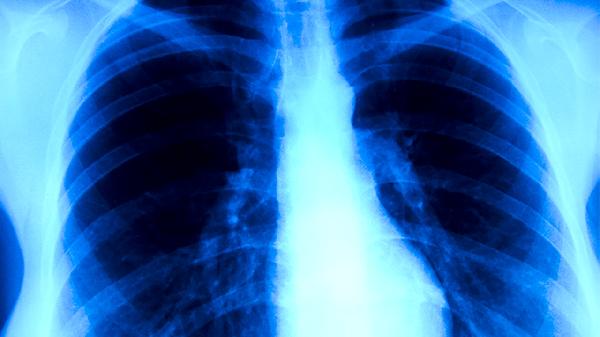

日常需注意咳嗽禮儀,打噴嚏時(shí)用肘部遮擋。出現(xiàn)持續(xù)咳嗽、低熱、盜汗等癥狀超過(guò)2周應(yīng)及時(shí)就診排查。高危職業(yè)人群建議每年進(jìn)行胸部X線檢查。預(yù)防性治療期間應(yīng)定期監(jiān)測(cè)肝功能,避免飲酒和食用富含酪胺的食物。通過(guò)綜合防控措施可有效阻斷結(jié)核病傳播鏈。